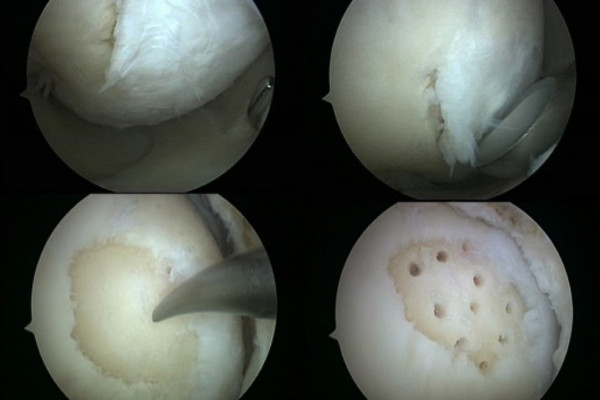

Technik der Mikrofrakturierung

Kleine, scharfbegrenzte, tiefergehende Defekt des Knorpels können durch einen sogenannten Mikrofrakturierung oder auch Nanobohrungen gedeckt werden. Hierbei werden zunächst alle losen Knorpelbestandteile entfernt und ein klar begrenzter Defekt geschaffen. Anschließend wird der freiliegende Knochen mit kleinen Meißeln oder Bohrern punktuell eröffnet.

Das aus dem Knochenmark austretende Blut ist reich an Stammzellen (Zellen die die Fähigkeit besitzen sich je nach Bedarf in unterschiedliche, spezialisierte Gewebezellen zu verwandeln) und füllt den Defekt zunächst mit einem Blutklumpen (Koagel) auf. Durch den Kontakt mit der Gelenkflüssigkeit und die im Gelenk herrschenden Scher- und Druckbelastungen wandelt sich dieses Blutkoagel in Ersatzknorpel (Faserknorpel) um und füllt den Defekt so auf. Dieser Eingriff erfolgt minimalinvasiv im Rahmen einer Gelenkspiegelung. Zum Schutz des sich neu bildenden Knorpels ist eine Entlastung für 6 Wochen mit einer anschließenden langsamen Belastungssteigerung erforderlich.